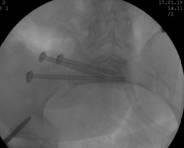

术中C臂